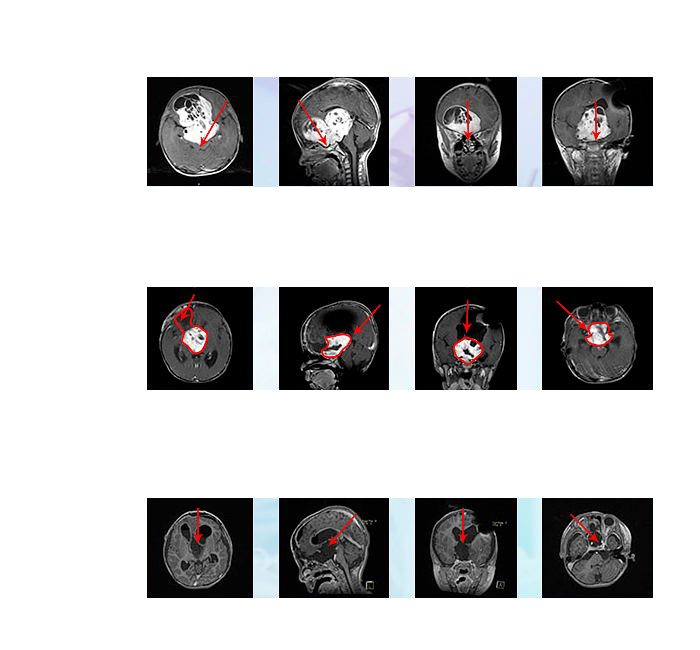

德国INI手术过程:小冬较初在北京首诊为“额叶胶质瘤”,但后在德国确诊为“视神经胶质瘤”,治疗方案和手术入路也都有了很大变化。为保全小冬的视力,主刀医生通过额骨颅骨开颅术和大脑半球间穹窿入路肿瘤切除术直至Monro孔(室间孔),并沿着脑室壁向中脑行进。小冬右侧的视神经被肿瘤浸润包裹,但是左侧视神经被小心地从肿瘤肿块中剥离出来,垂体腺和垂体柄也被小心的保护起来。

德国INI术后:术后患儿有一过性发热和尿崩,均很快控制好转,一周后出ICU病房,术后2周左右患儿视力有轻微好转,2周后出院,且能站立和短距离行走,较入院前好转明显。2019年4月复诊时未见复发,且视力逐渐恢复,可以分辨人影和准确抓拿物品。患儿脑肿瘤得到了大概率以上的切除,术前岌岌可危的视力也保住了。术后病理显示毛细胞型星形细胞瘤,WHO I级,低级别胶质瘤,研究显示其中位生存期可长达50年,肿瘤近全切手术之后可与正常孩子生存时间无异。

此次在德国INI的二次手术,从术前侵袭至双侧额叶及三脑室的较大瘤体,到术后影像上未见瘤体,从几近失明到逐渐地视力恢复接近正常,小冬的手术效果可以说是教科书级的示范案例。